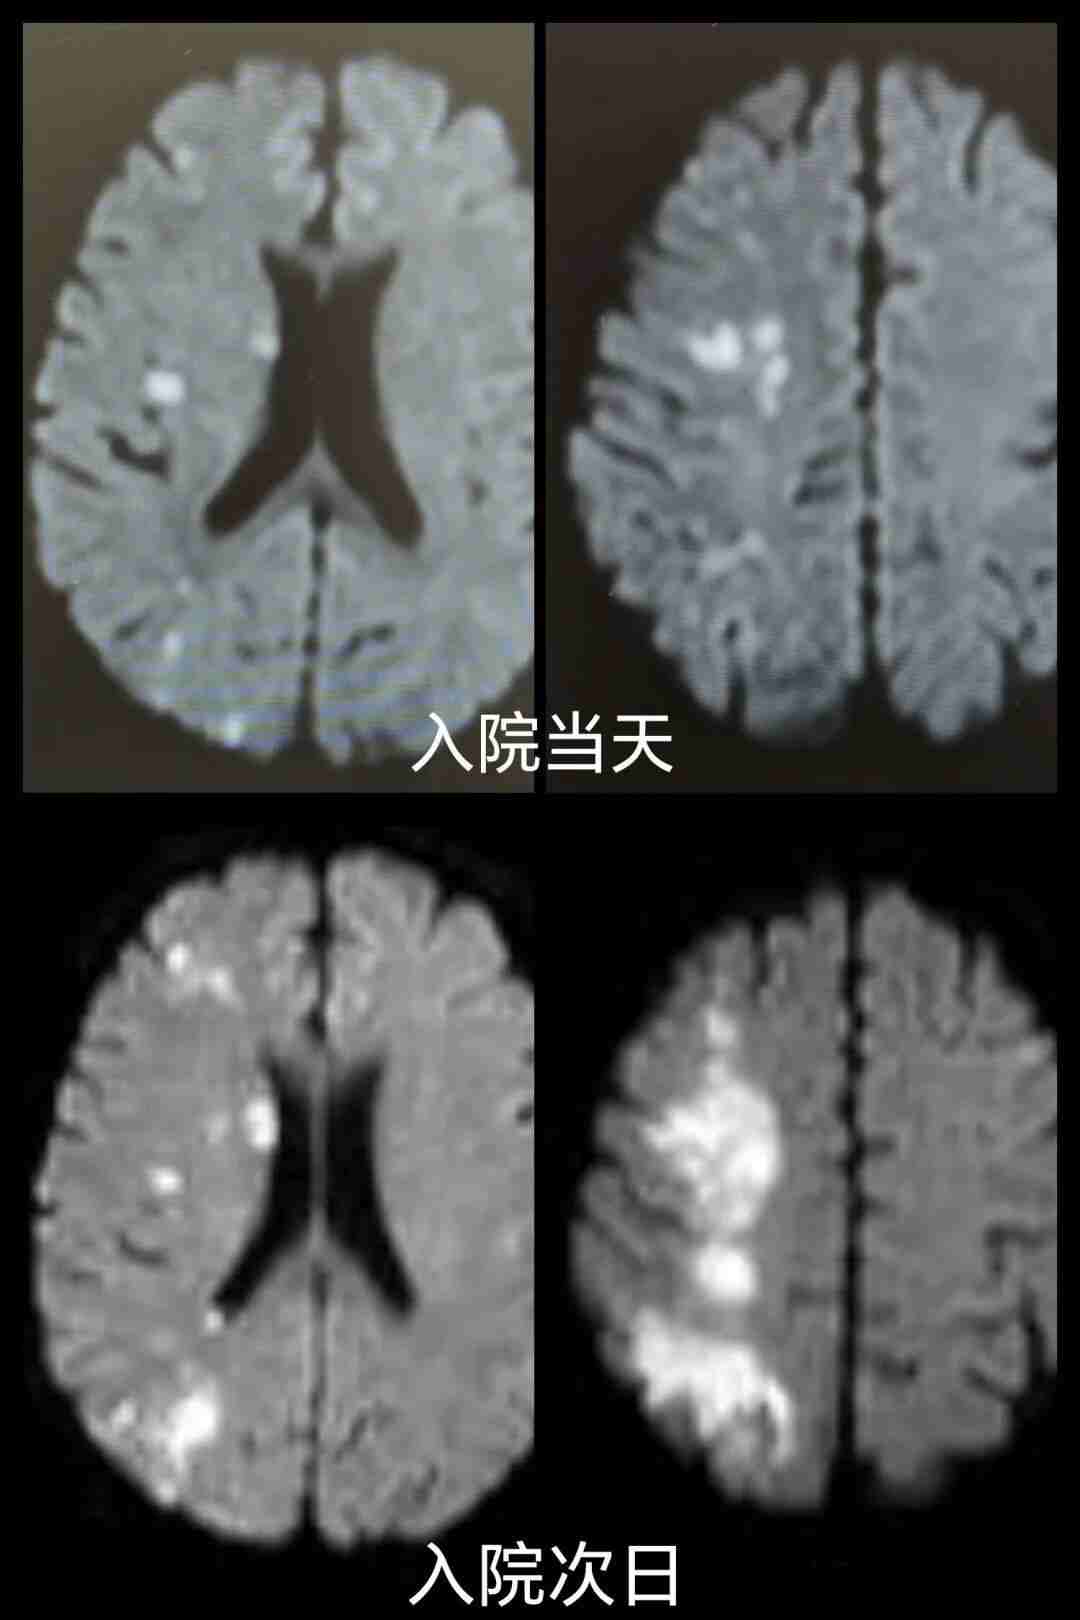

头部核磁共振检查提示:“右侧额顶枕叶急性缺血性脑梗死。”

次日,患者突发左侧肢体活动障碍,症状显著加重,考虑为急性缺血性脑卒中进展。

再次复查头部核磁共振,结果显示:“右侧额顶枕叶、侧脑室旁急性缺血性脑梗死,较昨日梗死体积明显增大。”